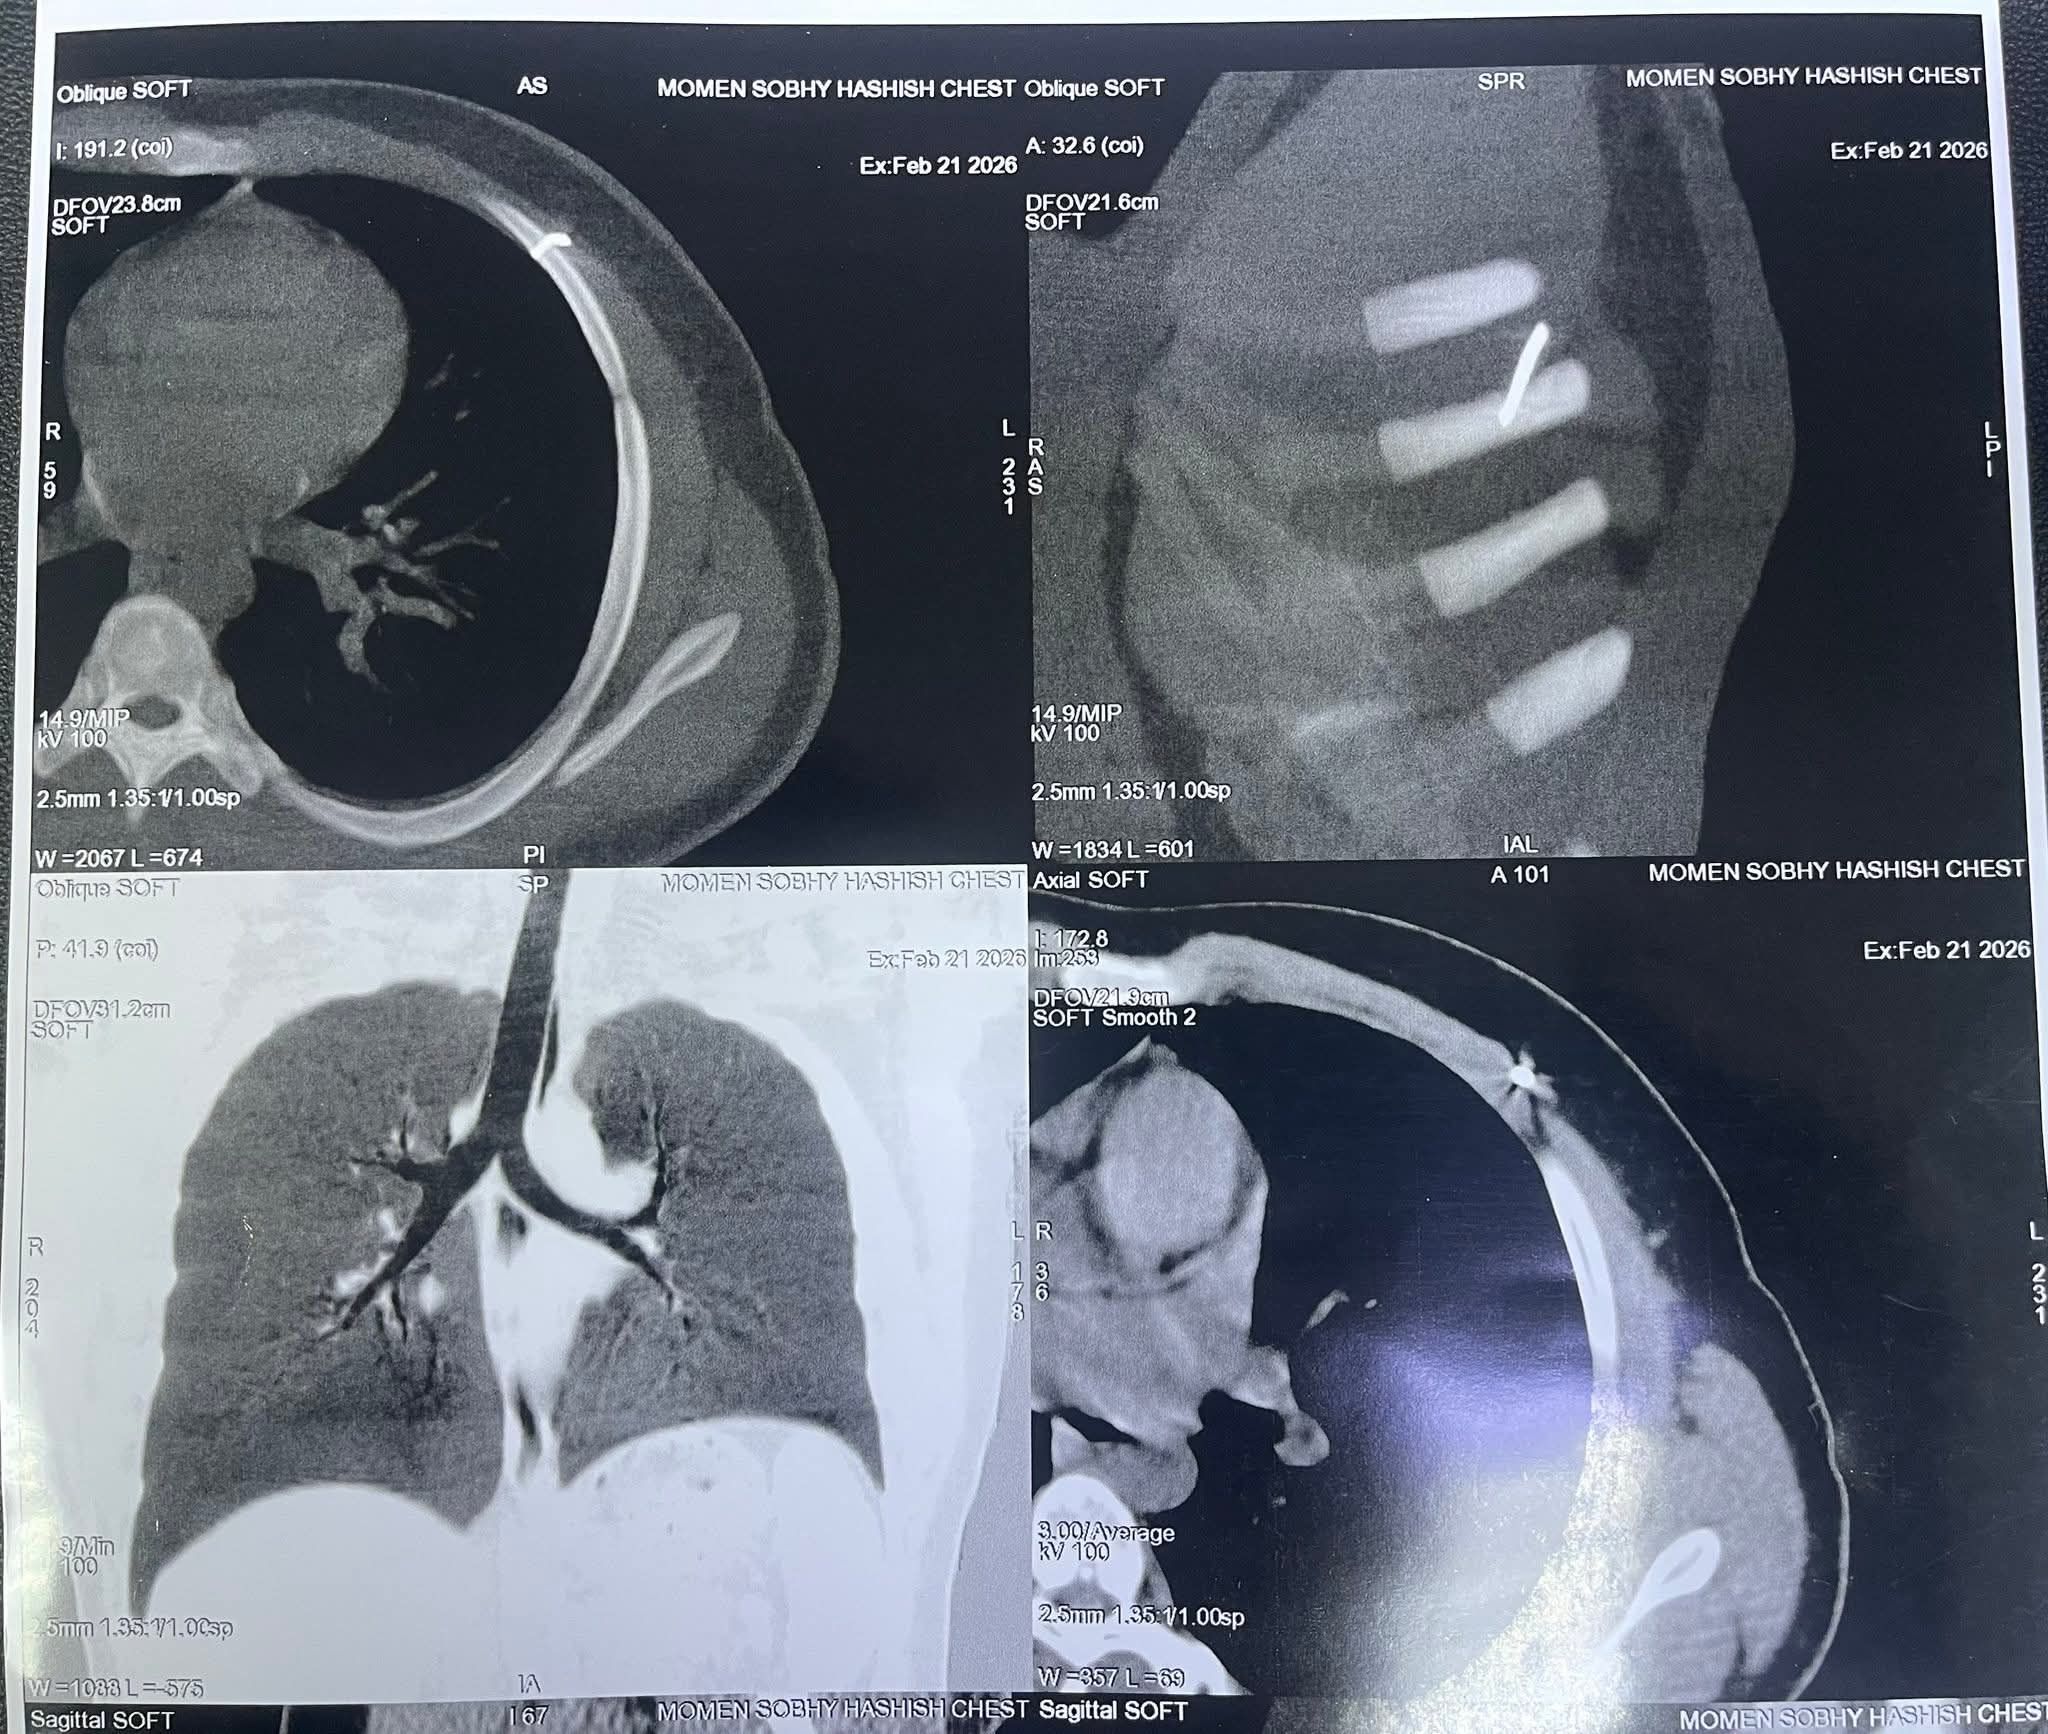

تفاصيل الجراحةوأضاف أنه بعد إجراء الإشاعات اللازمة تبين استقرار المسمار في أحد الضلوع وحدوث اعوجاج بالمسمار ليستقر بالضلع الخامس الجانب الأيسر من الصدر.

وأكد أنه تم استئصال المسمار باستخدام جهاز C- arm وعمل فتحة لا تتجاوز 1سم واستخراجه جراحيا في تدخل استغرق 10 دقائق، بمشاركة الدكتورة أية مشعل طبيبة التخدير، وتم الاطمئنان على الحالة الصحية للمصاب.

الأشعة توضح مكان المسمار